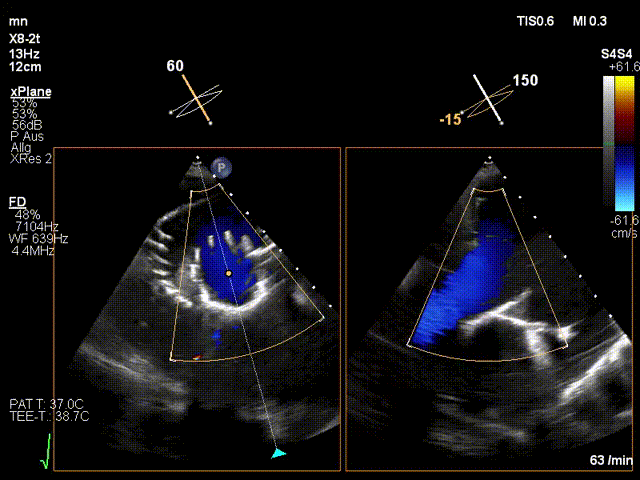

近日,德國慕尼黑大學(xué)Jörg Hausleiter教授團(tuán)隊(duì)成功應(yīng)用LuX-Valve Plus經(jīng)血管三尖瓣置換系統(tǒng)救治了一例因三尖瓣大量反流導(dǎo)致的右心衰竭患者,術(shù)后超聲顯示人工三尖瓣位置固定滿意,瓣架穩(wěn)定,無反流和瓣周漏?;颊咴谑中g(shù)室即刻拔除氣管插管,血流動力學(xué)改善顯著,LuX-Valve Plus經(jīng)血管三尖瓣置換系統(tǒng)的治療效果優(yōu)異。

LuX-Valve Plus經(jīng)血管三尖瓣置換系統(tǒng)本次“出海”圓滿完成,術(shù)后Jörg Hausleiter教授對LuX-Valve Plus經(jīng)血管三尖瓣置換系統(tǒng)的器械性能和治療效果大為稱贊,認(rèn)為LuX-Valve Plus的手術(shù)體驗(yàn)非常好。術(shù)后即刻超聲顯示三尖瓣反流消失,血流動力學(xué)改善顯著,患者恢復(fù)快。Anson Cheung教授也肯定了LuX-Valve Plus術(shù)中操作的便捷性,認(rèn)為LuX-Valve Plus容錯率高,對術(shù)中影像的依賴較小,后期希望可以更多的應(yīng)用LuX-Valve Plus三尖瓣置換系統(tǒng)于臨床實(shí)踐,讓更多的三尖瓣重度反流患者盡早獲益,改善預(yù)后。